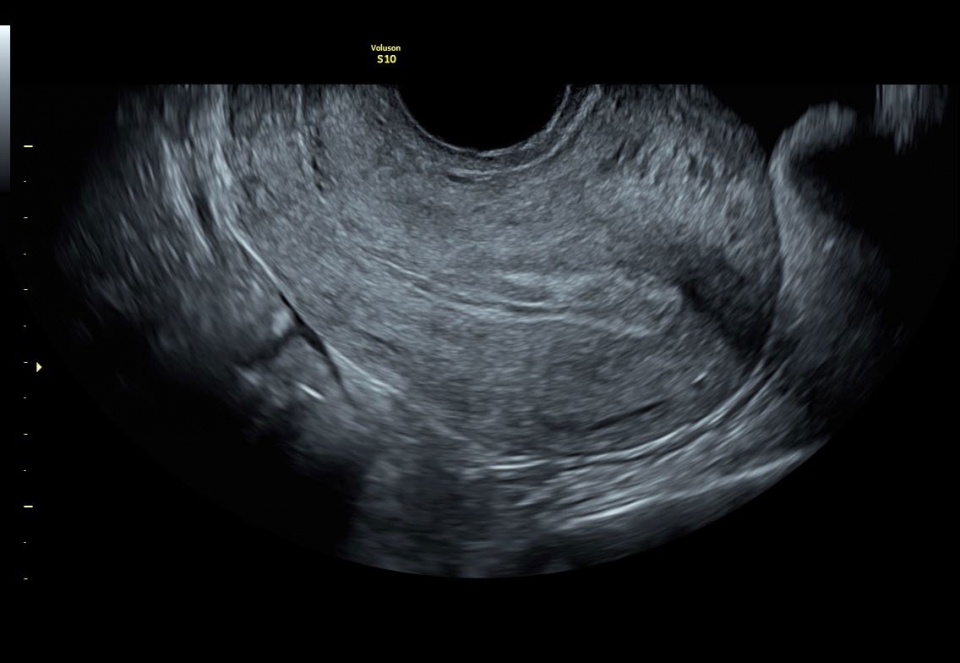

Ультразвуковая система Voluson S10 - это специальное медицинское оборудование, разработанное с учетом раннего выявления патологий и заболеваний женского здоровья, начиная от оценки самочувствия матери и заканчивая состоянием плода. Гинекологическое наблюдение на всех этапах беременности является неотъемлемой частью нормального процесса развития ребенка и предсказуемых родов.

Ультразвуковой аппарат Voluson S10 оснащен чувствительным цветовым допплером, который позволяет оценить кровоток и анатомию сосудов, обеспечивая полную информацию о состоянии плода и околоплодной жидкости. Кроме того, на Voluson S10 установлен большой 22-дюймовый экран, который при использовании трехмерного шарнира может поворачиваться в различных плоскостях, обеспечивая удобство как для пациента, так и для врача.

Гинекология: